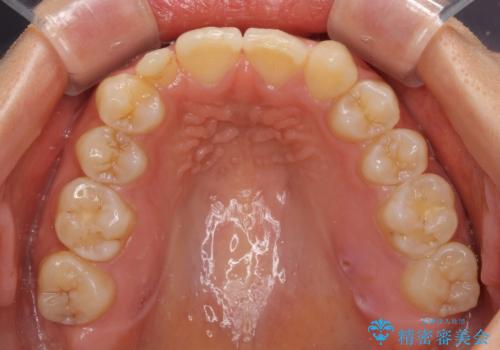

- 他院で矯正治療を終え、上顎前から2番目の歯の大きさを気にして来院された患者様です。

右側は小さく、左側は欠損により犬歯が前から2番に来ている状態でした。

矯正治療の段階で、矮小歯は前後にスペースが作ってあったため、極力左右対称の歯冠形態となるように補綴治療を行うこととしました。